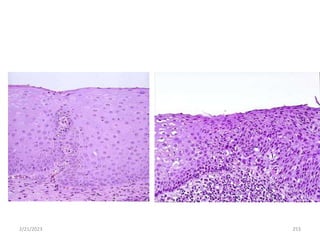

Squamous cell carcinoma

2/21/2023 219